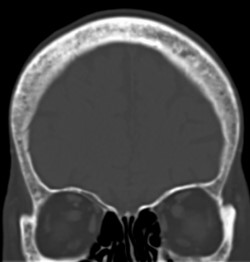

CTの骨条件では、頭蓋骨に不均一な骨硬化像を認める。

頭部単純CT

<骨病変>

• 大腿骨遠位と脛骨近位に左右対称性の骨硬化